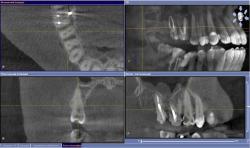

• Горизонтальные срезы через устьевую часть и среднюю треть:

щелевидный вход и 2 корневых канала (рис. 57-60).

| Рис. 57-58 Горизонтальный срез через устьевую часть 1.5 зуба; выделенные фрагменты и 3-D визуализация (3-D Interactive Tooth ATLAS): щелевидный профиль корневого канала |

| Рис. 59-60 Горизонтальный срез через устьевую и среднюю треть 1.5 зуба; выделенные фрагменты и 3-D визуализация: два устья |